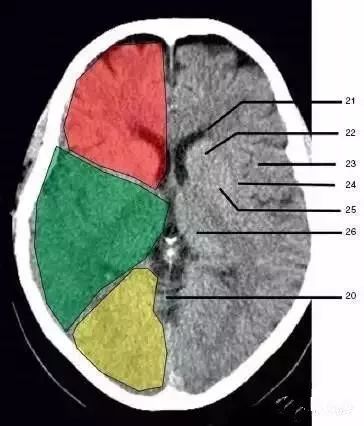

21、侧脑室前角 (Frontal horn of lateral ventricle)

21a、第三脑室 (Third ventricle):绿色部分为颞叶(Temporal Lobe),浅红色部分为额叶(Frontal Lobe),黄色部分为枕叶(Occipital Lobe)

22、尾状核头部(Head of caudate nucleus)

23、岛叶(Insular cortex)

24、外囊(External capsule)

25、豆状核(Lentiform nucleus)

26、丘脑(Thalamus) :绿色部分为颞叶(Temporal Lobe),浅红色部分为额叶(Frontal Lobe),黄色部分为枕叶(Occipital Lobe)